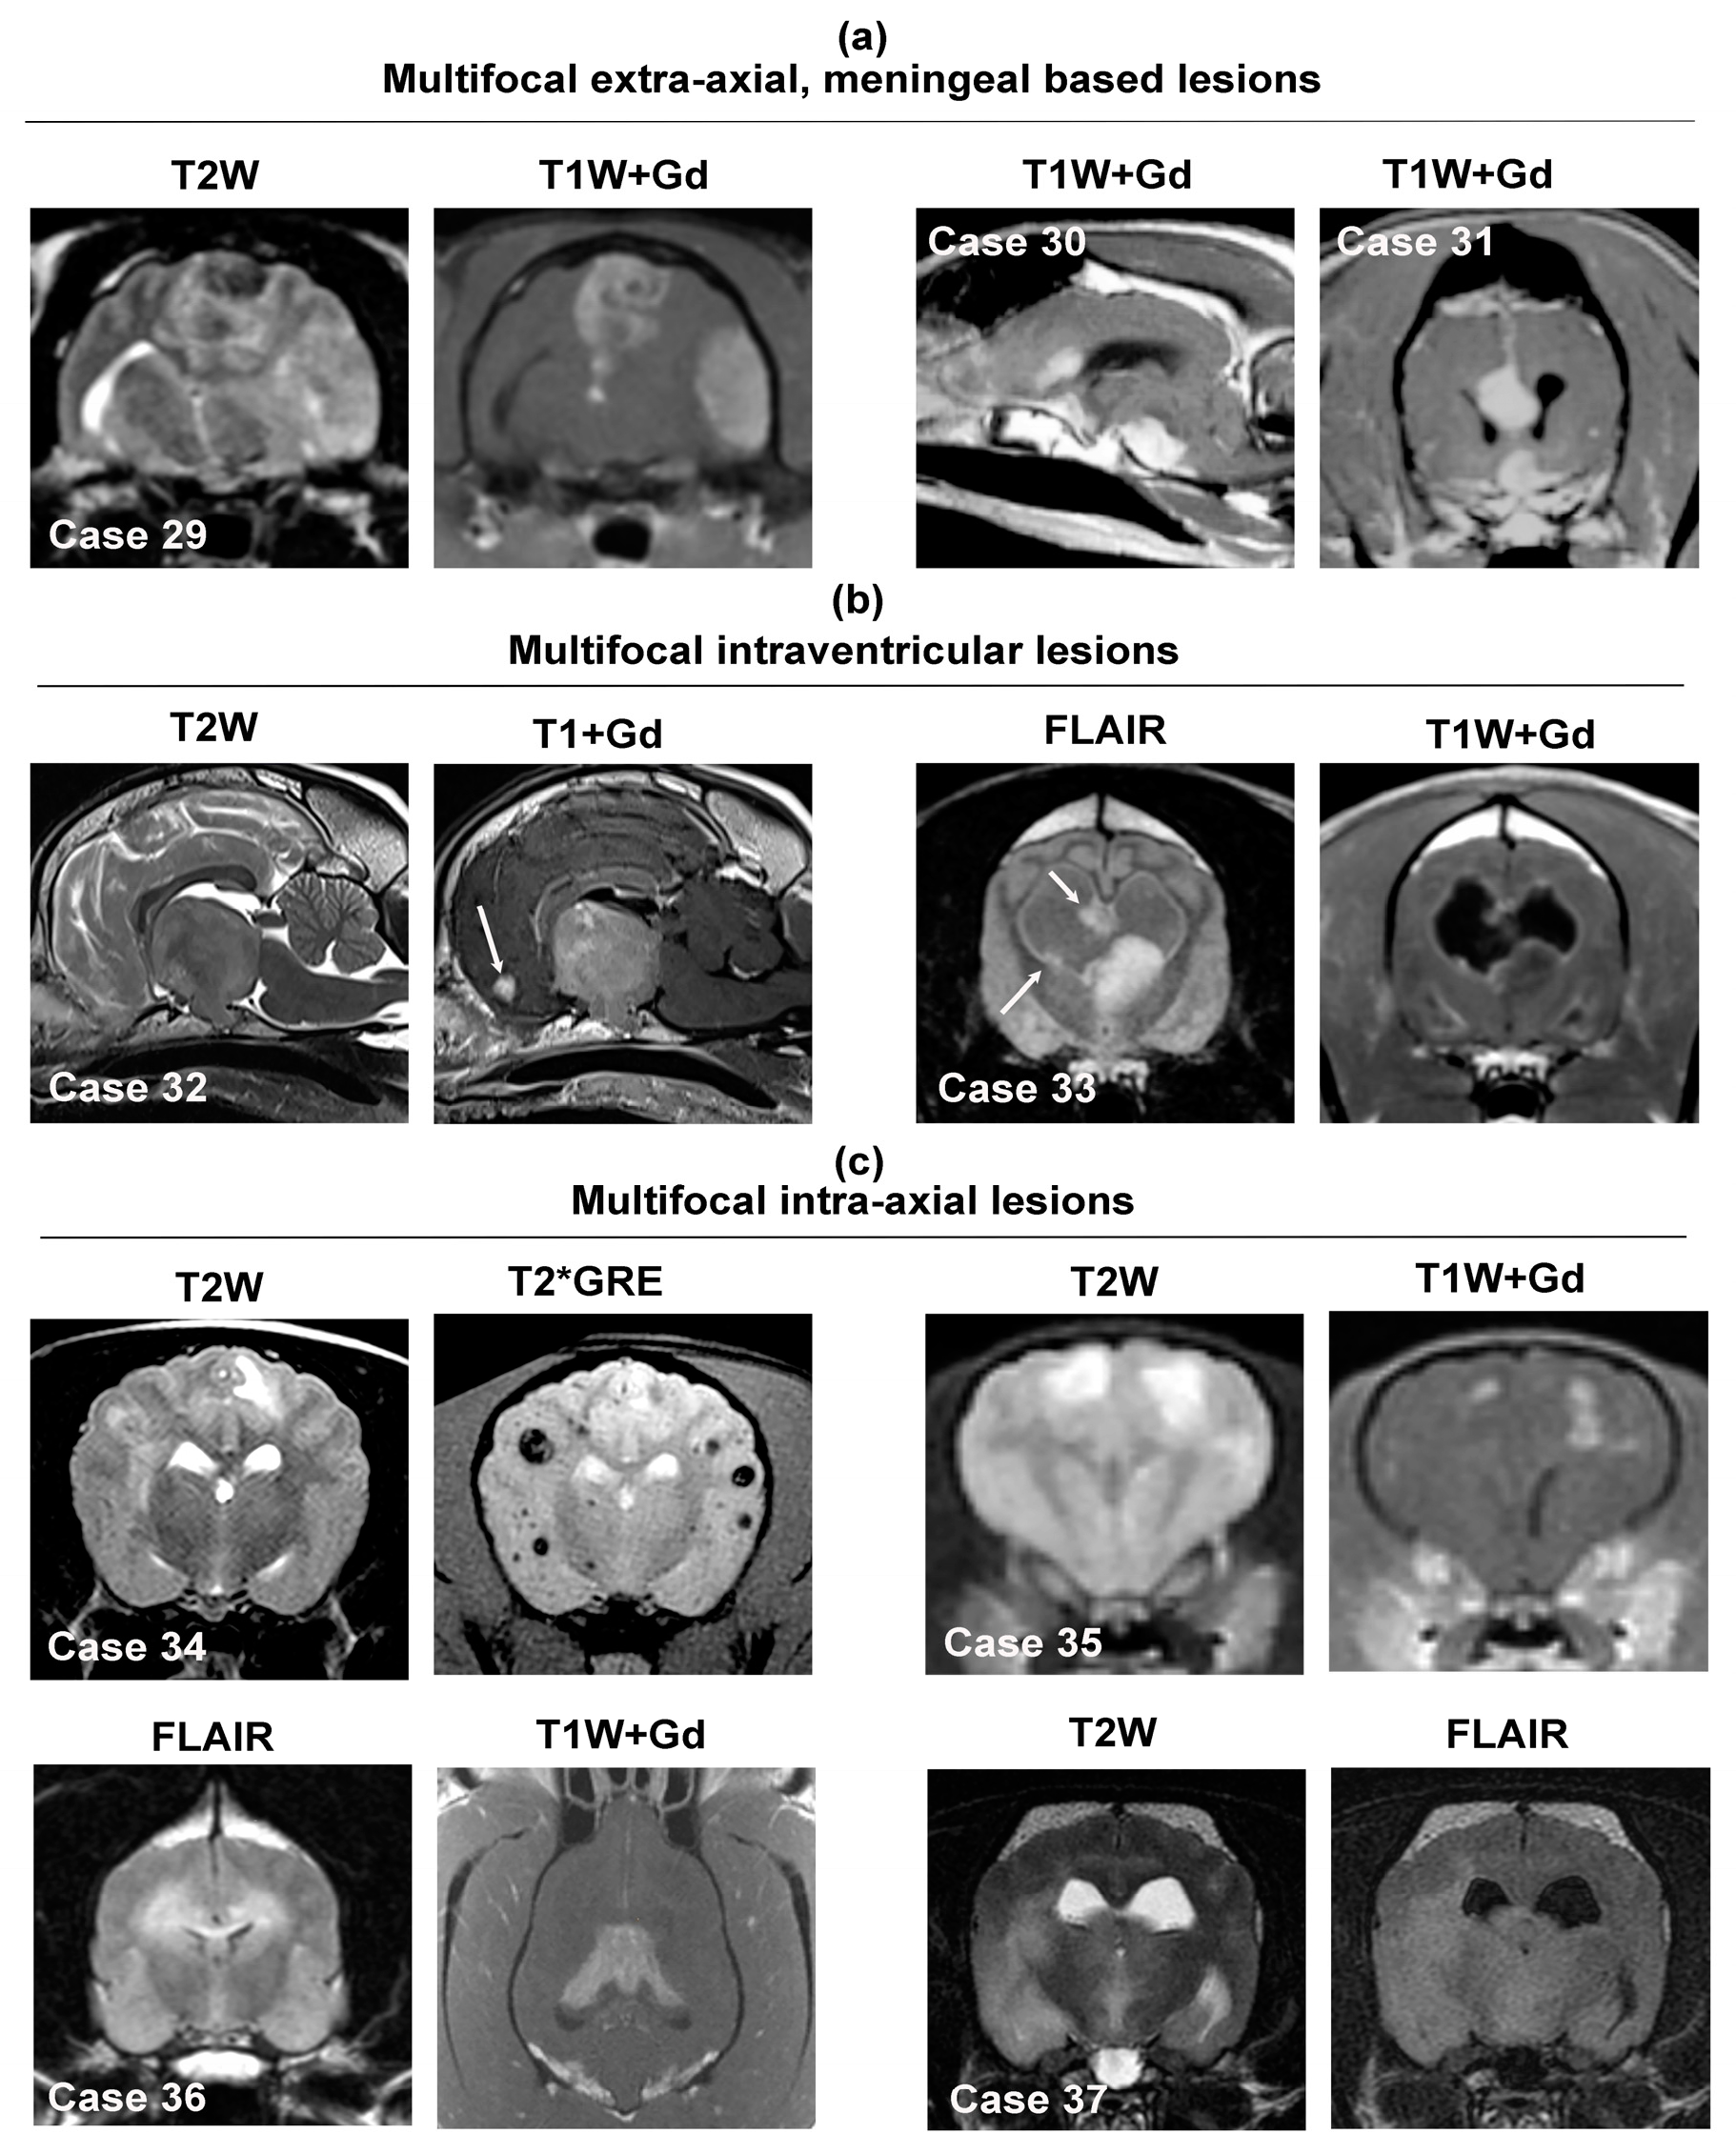

MRI features of multifocal intracranial neoplastic lesions. Multifocal extra-axial meningeal-based lesions appear in (a), multifocal intraventricular tumors in (b), and multiple intra-axial lesions in (c). Case 29—feline, multifocal parasagittal and cerebral convexity meningiomas. Case 30—canine multifocal extra-axial HS involving the falx cerebri and basilar region. Case 31—canine multifocal, uniformly contrast-enhancing falcine and parasellar meningiomas. Case 32—canine 3rd ventricular choroid plexus carcinoma with contrast-enhancing drop metastasis within the rostral horn of the lateral ventricle (arrow). Case 33—canine intraventricular high-grade oligodendroglioma with multiple ependymal drop metastases (arrows). Note the lack of suppression of the CSF signal on the FLAIR image. Case 34—canine multiple cerebral hemangiosarcoma metastases, which appear as heterogenous, round, variably sized T2W lesions that demonstrate susceptibility artifact on the T2*GRE sequence. Case 35—canine multifocal urothelial carcinoma metastases within the cerebrum; the metastatic foci or T2W hyperintense and demonstrate contrast enhancement. Case 36—canine ‘butterfly’ glioblastoma (high-grade astrocytoma) with bilaterally symmetric involvement of the subcortical white matter and corpus callosum. Case 37—canine gliomatosis cerebri manifesting as poorly defined T2W/FLAIR hyperintensities within the parietal, temporal, and piriform lobes and thalamus.

The major differential diagnostic considerations for multifocal intracranial neoplastic lesions are provided in Table 3. Several of the neoplasms that may present with multifocal mass lesions represent occasional to rarely observed variants of primary brain tumors that typically appear as solitary mass lesions (Figure 8, Cases 29–31) and were reviewed in Section 3.1, Section 3.2, Section 3.3 and Section 3.4. In these instances, other than the multifocal lesion distribution, the other imaging features and signal characteristics of these tumors are similar as to when they appear as solitary masses, and thus, only notable differences in lesion appearances or new tumor types from what have previously been covered are discussed in the sections below.

This imaging presentation is predominantly caused by hematogenous metastases of systemic neoplasms such as hemangiosarcoma, carcinomas, or melanoma [4]. Intra-axial metastatic lesions are preferentially found in the telencephalon and typically with a distribution at gray-white matter interfaces. Metastatic hemangiosarcomas frequently present as poorly defined, heterogeneous lesions in all sequences, with many lesions containing susceptibility artifact on T2*GRE or SWI (Figure 8, Case 34), associated with moderate to severe perilesional edema, and demonstrate moderate to strong heterogeneous or ring-type contrast enhancement [12,14,82]. Metastatic carcinomas also appear as ill-defined lesions that may be T1W hypo- to iso-intense, T2W/FLAIR hyperintense, and are typically contrast enhancing, although the degree and patterns of contrast enhancement can vary significantly (Figure 8, Case 35). Unlike hemangiosarcoma, metastatic carcinoma lesions are not usually associated with imaging evidence of intratumoral hemorrhage. As melanin is a paramagnetic substance, melanomas may appear as hyperintense lesions on T1W sequences. Gliomas can manifest as bilaterally symmetric or asymmetric lesions with involvement of both cerebral hemispheres and the corpus callosum (i.e., butterfly glioma; Figure 8, Case 36), asymmetric multifocal to diffuse ill-defined parenchymal lesions (i.e., gliomatosis cerebri; Figure 8, Case 37), or multiple, discrete intra-axial masses (i.e., satellite lesions), all of which represent different manifestations of intraparenchymal glioma spread [70,71,72,75,76]. A notable characteristic of gliomatosis cerebri is its tendency to lack contrast enhancement [72,76].

3.5.2. Multifocal or Diffuse Intraventricular Lesions

Multifocal intraventricular lesions most often result from drop metastases of choroid plexus carcinomas or gliomas with intraventricular involvement [70,71,81]. Choroid plexus carcinoma drop metastases are usually contrast-enhancing (Figure 8, Case 32), whereas glioma-associated drop metastases (Figure 8, Case 33) may have imaging characteristics that differ from the primary lesion, including a conspicuous lack of contrast enhancement of many lesions [71,81]. Lymphoma may also manifest with diffuse contrast-enhancing ependymal and periventricular lesion patterns [58,87].